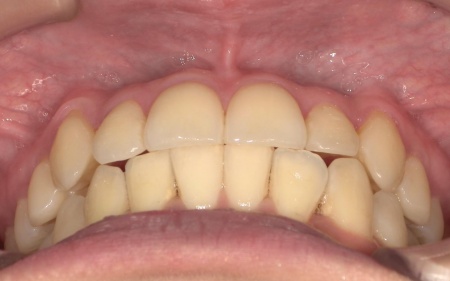

20代女性 八重歯と歯並びの乱れをマウスピース矯正装置で改善した症例

患者様の場合は上下あごの位置関係から噛み合わせに大きな問題はなく、横顔のバランスや鼻先とあごを結んだEラインにも目立った乱れは見られませんでした。

そのため、歯の位置や傾きを整えることで歯並びを改善できると診断しました。

矯正治療終了後、歯並びの後戻りを防ぐための保定装置を装着していただきました。

経過観察を行い問題がないことを確認して、治療を終了しました。